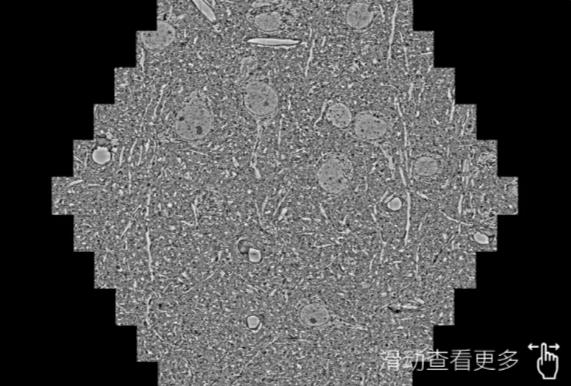

鼠脑切片。左图使用河北蔡司河北扫描电镜MultiSEM706对165μmx143pm面积区域成像,耗时仅需1.5秒。右图为鼠脑切片中30μm区域放大效果。样品由芝加哥大学B.Kasthuri提供。

使用蔡司高速河北扫描电镜MultiSEM对1mm²人脑皮层组织进行高分辨成像,并对其中的各种细胞结构进行三维重构分析。左图展示了2x3mm²组织平面中锥体神经元的三维重构效果。右图显示了局部体积神经元三维重构。图像由哈佛大学chtman实验室提供,渲染图由D. Berger 制作。